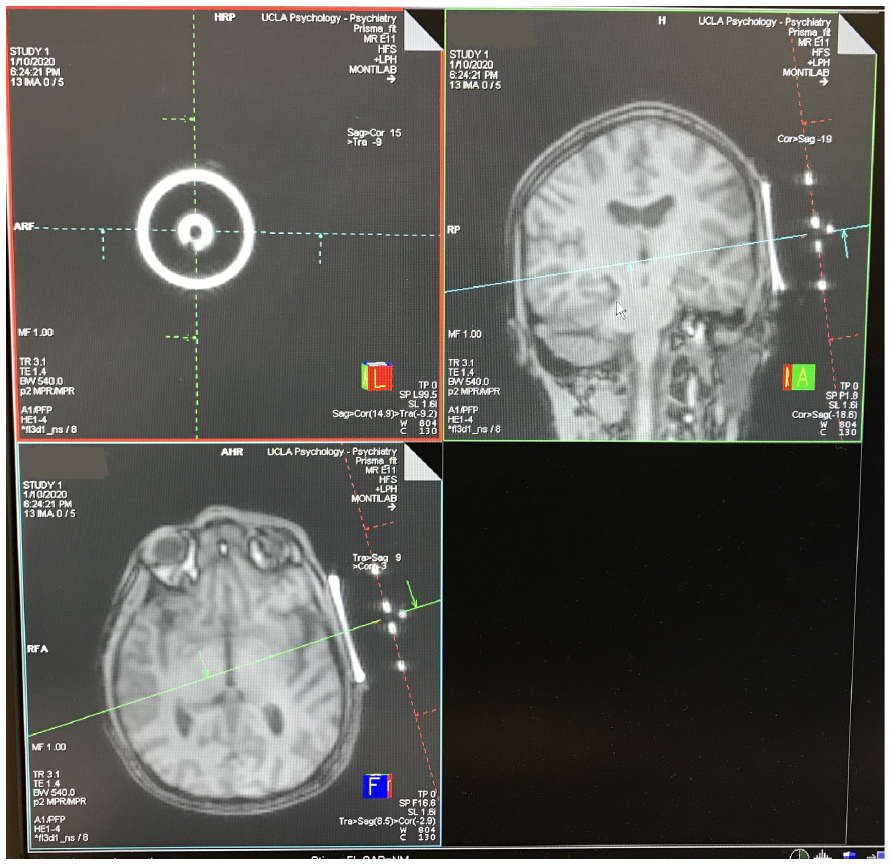

下方中間圖像顯示對齊過程。

下方右側圖像顯示焦區的大約位置(黃色橢圓)(Schafer 2021)。